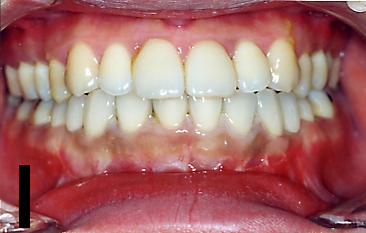

受け口セットバック手術の症例

症例 1

| BEFORE | AFTER |